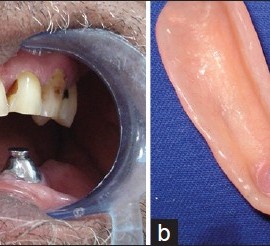

Ксеростомия — сухость слизистой оболочки полости рта вследствие снижения и уменьшения выделения слюны. Возможны два вида нарушения слюноотделения. Ксеростомия связана с патологическими процессами в слюнных и слизистых железах ротовой полости либо она возникает на фоне общих заболеваний. Причинами, вызывающими ксеростомию, являются воспалительные и дистрофические заболевания слюнных желез, а также опухоли. […]